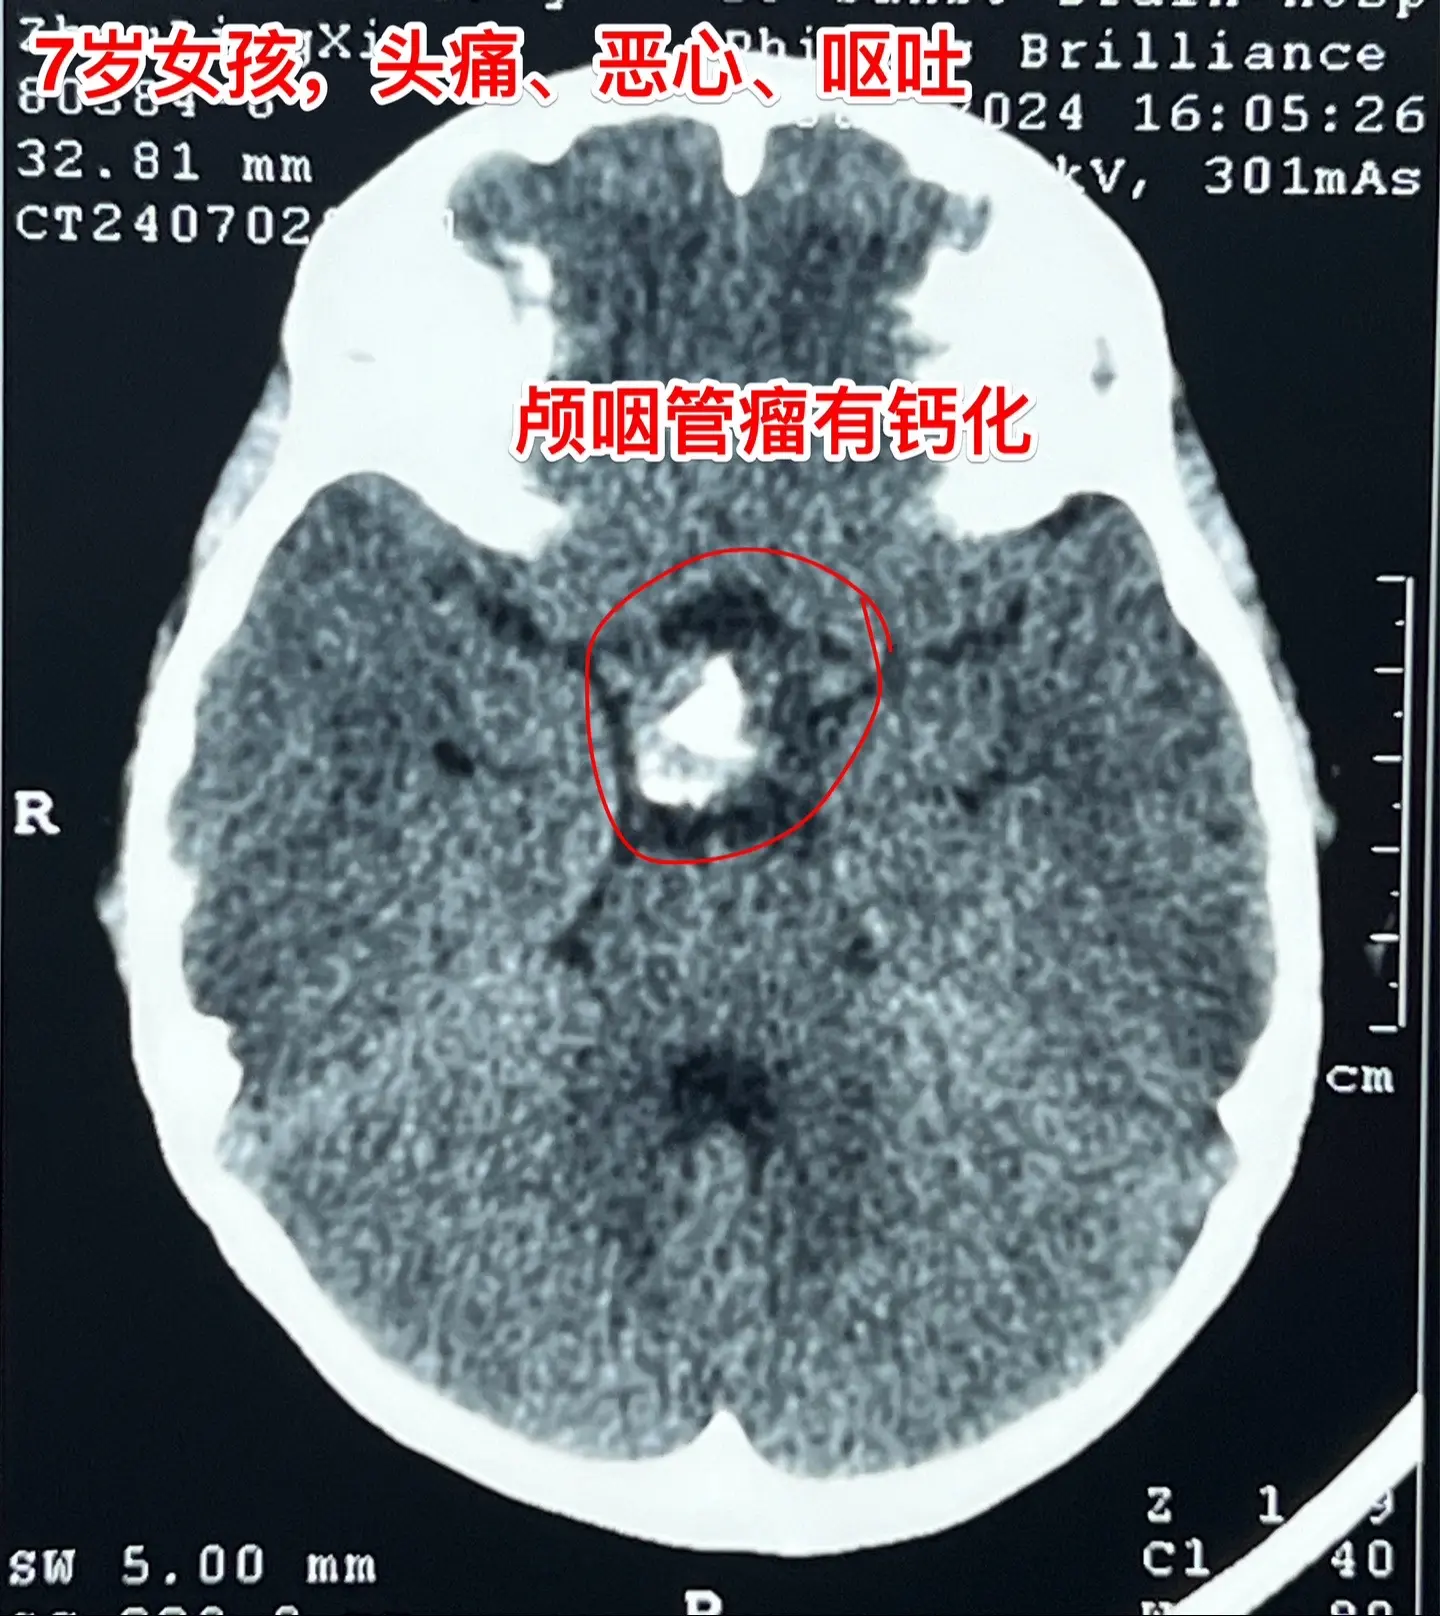

头痛、恶心、呕吐,是颅内高压症状!7岁江西上饶的小女孩,一个月前感头痛、恶心、呕吐。这是颅内高压的症状。他们到就近的医院就诊,作头部CT和磁共振,发现了颅咽管瘤,这个颅咽管瘤造成了梗阻性脑积水,颅内高压,所以小孩子出现头痛、呕吐症状。 根据头CT可以看见肿瘤内有钙化,可以确诊是典型的造釉细胞性颅咽管瘤。这样的肿瘤造成的脑积水,一般在切除肿瘤后就可以自愈,不需要专门作脑积水的手术。 2024年7月12日作了手术,肿瘤得到完全切除。 目前小孩子身体状况很好,快要出院了。